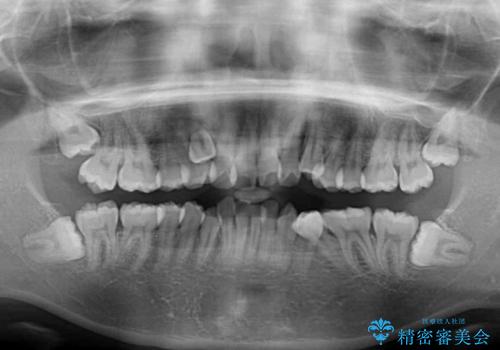

- 前歯の著しい叢生や八重歯を気にして来院された患者様です。

上下の顎がずれており、上下の正中は歯1本分の差がありました。

上下左右の小臼歯4本を抜歯し、極力正中を合わせるように矯正治療を始めていくこととしました。